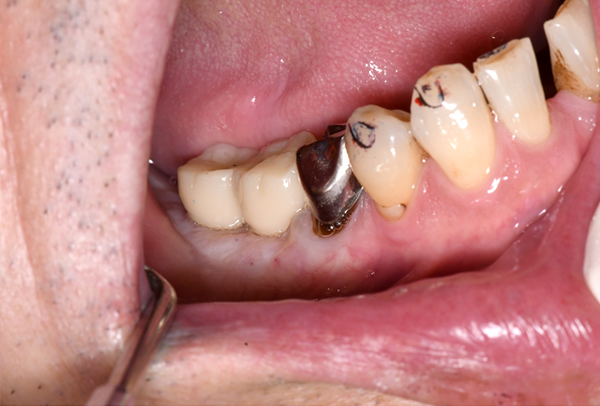

症例4. 歯冠長延長術

![]() |

| 歯平面が傾いてしまっています。 | 歯茎を下げる手術を行いました。 |

| 歯茎が綺麗に治りました。 | 平面も整って綺麗に被せ物が入りました。 |